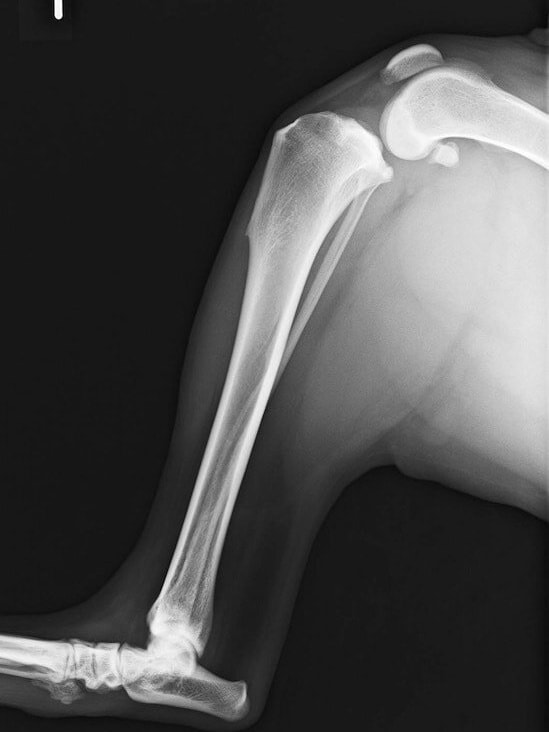

アメリカンコッカースパニエル 5歳

半年にわたる左後肢の跛行が認められるとのことで来院されました。触診にて左膝関節の疼痛、内側部の腫脹、膝蓋骨の内方脱臼を認めました。レントゲン検査にてfat pad signを伴う関節炎が認められたことから、前十字靭帯断裂と膝蓋骨内方脱臼( GradeⅢ)の併発と診断し、手術を行いました。術中の関節鏡検査にて前十字靭帯の完全断裂を確認、関節液検査にて感染を除外した後、TPLOと、滑車溝形成を始めとした膝蓋骨脱臼整復術を実施いたしました。

術前側面像

術前正面像

術前に25°であったTPAは、TPLO実施により7°に矯正されました。症例の歩行状態は良好です。